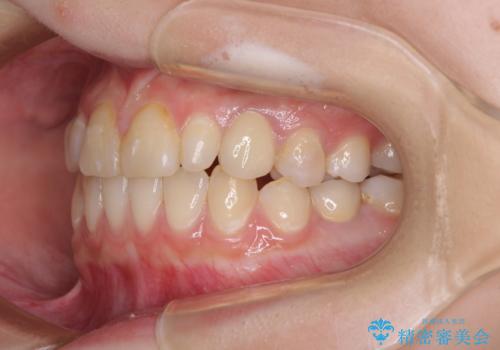

欠損と残存乳歯 矯正治療とインプラント治療

- 残存した乳歯や歯の欠損、歯並びを気にして来院された患者様です。

乳歯を残した状態は予後がよくないこと、矯正治療と補綴治療を総合的に進めていきたいとのことで、インビザラインによる矯正治療とインプラント補綴治療を並行して進めていくこととしました。